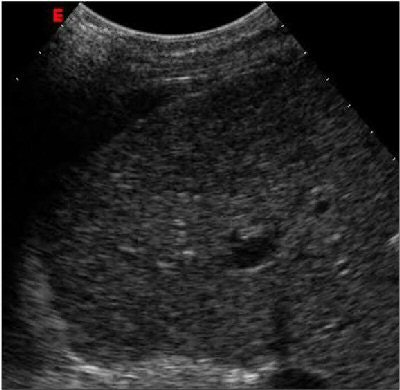

| Above: Unenhanced echocardiogram. Below: Echocardiogram enhanced with Definity (Bristol-Myers Squibb Medical Imaging, North Billerica, MA). Image courtesy of Bristol-Myers Squibb Medical Imaging. |